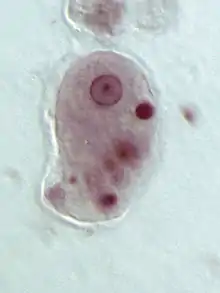

Le genre Entamoeba se caractérise par un noyau ayant l'aspect d'un anneau après coloration, avec une chromatine disposée en petit amas central (dit caryosome) et en couche périphérique.

Entamoeba histolytica peut se présenter sous deux aspects différents : le trophozoïte, forme cellulaire végétative mobile et de multiplication, et le kyste, forme immobile, de résistance et de contamination[11].

- Entamoeba histolytica histolytica, plus volumineuse, de 20 à 30 ou jusqu'à 40 µm. C'est une forme invasive, véritablement parasitaire, hématophage, qui envahit la muqueuse colique et peut migrer vers d'autres organes, en étant responsable de l'amœbose maladie.

Entamoeba histolytica histolytica présente le même aspect général que minuta, avec des caractères supplémentaires, comme la présence d'hématies en voie de digestion dans des vacuoles cytoplasmiques (d’où le nom d’histolytica)[11].

Le kyste (10 à 16 μm) est sphérique, entouré d'une enveloppe résistante. Initialement, un kyste immature contient une vacuole stockant du glycogène, des agrégats de ribosomes, et un noyau. Par division du noyau, le kyste mûrit en deux puis quatre noyaux pour devenir un kyste à pouvoir infectieux[16]. Il survit au minimum 10 jours à 18 °C, ou 3 mois à 4 °C, dans le milieu extérieur[17]. C'est la forme de dissémination, qui résiste bien aux agents chimiques.